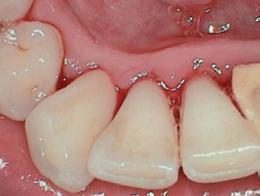

Dental hygienists independently utilize digital scanning for education and motivation. Not only can the clinician educate the patient with the images, but the patient has a visual that is easily understood. These images contain powerful visuals of attrition, fractured teeth, abfraction, gingival recession, overjet, and crowding.4 Biofilm can be displayed after the application of disclosing solution.5 Separate photos are not required to capture the biofilm present when using digital scanning.